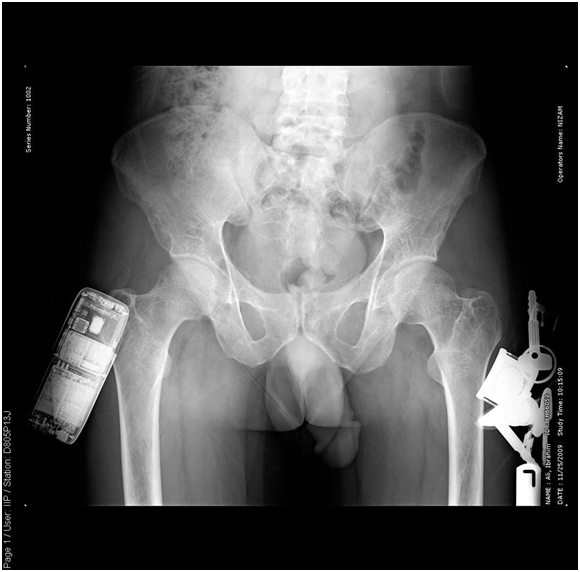

Pelvis –x-ray nov.22.2009

- R The Bones shows severe osteopenia, with appearance of Looser’s zones in the superior pubic rami, consistent with Osteomalacia…

Skeletal X-Ray: 6 months later

- Pelvis & both Femori: there is thickening of secondary bone trabeculae ,in the neck and metaphysis of both femori indicating osteopenia

- Upper Limbs & legs: normal cortical thickness but there is also thickening of secondary bone trabeculae in the distal tibia and fibula

- No Looser’s zones were detected.